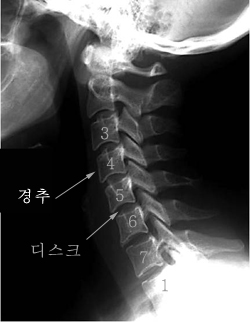

목 디스크는 목의 디스크(경추 디스크)에서 출현하는 질환으로, 경추 디스크 사이의 연골판이 터져 디스크 내부 물질이 경추 신경을 자극해 통증이나 저림증 등의 증상을 유발 해요. 목 디스크는 일상생활에서의 안 좋은 자세나 많은 운동, 부상 등이 이유가 되는 것이 될 수 있기도하고, 시간이 지날수록 발생 확률이 높아져요. 목 디스크의 증상으로는 목 부위의 통증, 팔의 저림, 근육 약화 등이 있으며, 증상이 난폭한 경우 수술 등의 치료가 필요할 수 있어요. 그리하나 대개의 경우 치료 없이도 시간이 지나면 증상이 호전되는 경우가 대부분입니다.

목디스크가 생겨나게 보면 어깨에서부터 팔을 지나 엄지손가락까지 저리고 아프게 되면서 7번과 8번 신경이 눌려지게 되어 손과 손가락 마디마디가 저리고 통증이 있고요. 이 통증이 팔, 어깨에서 손 및 손가락 등으로 방사하게 되고 있는데 이때 신경 분포에 따라서 대부분 5번 신경이 눌리게 되면서 어깨가 아프고, 6번 신경까지 눌리게 되면서 통증은 더 심해진다고 하더라고요.